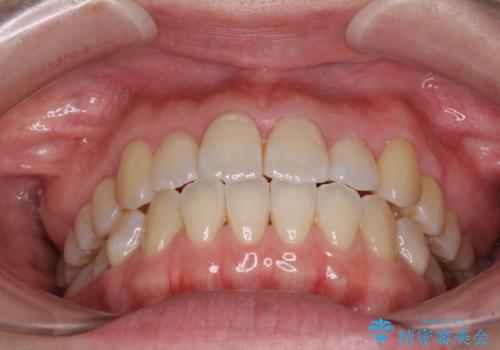

インビザラインでの歯列全体の後方移動は時間がかかりますが、しっかりと装着時間を守っていただいたので、スッキリとした口元に仕上げることができました。

親知らずを全て抜去し、歯列全体を後方に移動させることで口元の閉じにくさいを改善していくこととしました。